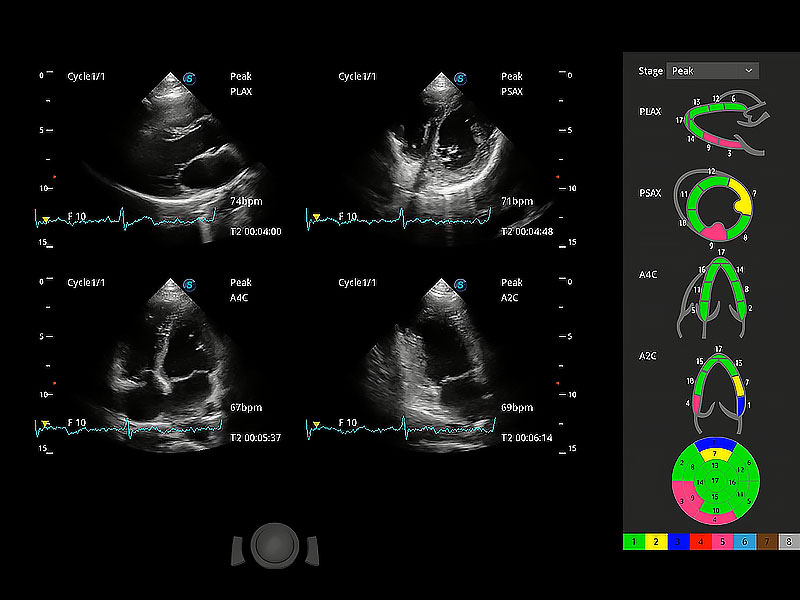

具備多種協(xié)議可選,同時(shí)支持17階段劃分法和專業(yè)的SE報(bào)告。